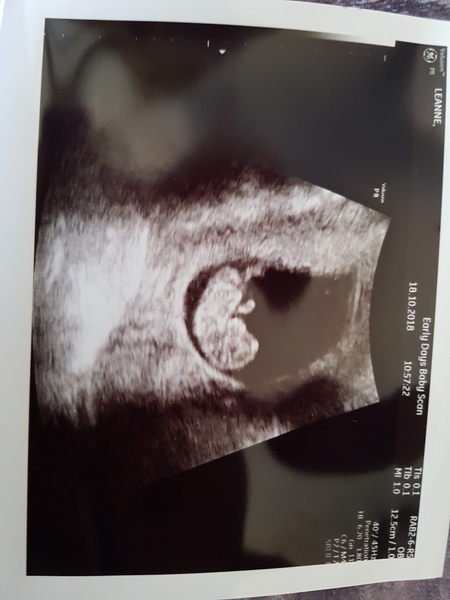

Apparently miracles happen!! I had loads of red blood and I mean alot and then a big clot which looked similar to my last loss. Just had a scan.. I know I'm not safe yet but wow. It was jumping around and waving and kicking. I'm in love and very shocked!! Better rearrange a booking in appointment 😂

@Junex88 yay! what amazing news, that is such a clear scan photo as well.